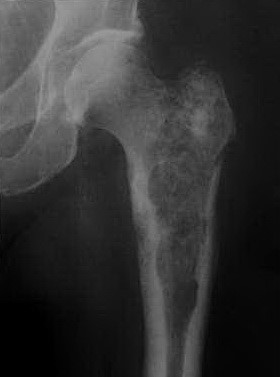

Перелом шейки. Определяется перестройка структуры эпифиза, метадиафиза кости, с появлением зон повышенной плотности, с нечеткими контурами. Расположены хаотично. Также определяются несколько участков разряжения костной структуры (лизис?). А это пациент какого пола? А другие кости не смотрели? Может МТС по смешанному типу.

Спасибо, Оля. патологический перелом есть. Пациент - мужчина, 40 лет, жалобы на боли в левом т/бедренном суставе в течении полугода. При скенировании - накопление только в левой бедренной кости. При исследовании по органам - без патологии. Собственно дифференцируем между хондросаркомой и энхондромой. Хотелось бы альтернативное мнение.

Но не в данном случае, поскольку здесь есть деструкция кости, узурация кортикала, обызвествления характерны для хрящевого матрикса и т.д. По биоптату были сомнения у морфологов, поэтому я спросила коллег, может ли помочь МРТ в диф. диагнозе

Я и забыл про эту публикацию! МРТ может и должно помочь, во всяком случае такое обширное снижение сигнала от костного мозга явно указывает на злокачественную природу поражения.

Но, отвечая на Ваш вопрос, на МРТ можно с очень большой достоверностью сказать, есть ли признаки злокачественности. По тем изображениям сразу было понятно, что имеем дело со злокачественной опухолью, вероятно хондросаркомой с патологическим переломом головки.

Почему и какие это признаки? Основной при МРТ - признак инфильтрации костного мозга. Лучше всего его выявляют в Т1 последовательности (нижнее изображение) и выглядит, как снижение интенсивности сигнала от кости, т.е. костный мозг выглядит темным, приблизительно, как мышцы. Инфильтрация костного мозга также хорошо выявляется в последовательности STIR - это последовательность инверсии восстановления с подавлением сигнала от жира. На STIR патологически измененная кость дает повышенный сигнал (т.е. яркий), в то время, как остальные кости и жировая клетчтатка мягких тканей темные. В Вашем случае, это второе снизу изображение, но. как Вы видите, сигнал повышен неравномерно и не очень яркий. Это связано с наличием обызвестленного матрикса.

Есть еще один нюанс, по поводу STIR - сигнал повышается не только при инфильтрации, но любом отеке (неспецифическом, травме, инфекции), а также яркий сигнал в кости будет от структур с высоким содержанием воды - начиная от кист и заканчивая хрящевыми доброкачественными образованиями. Поэтому, основной последовательность, для выявления опухолевой инфильтрации кости всегда является Т1. Если на Т1 взвешенных изображениях, сигнал от костного мозга не снижен, а на STIR повышен, то вероятнее всего имеем дело с доброкачественным процессом.

Второй признак на МРТ - наличие патологического/мягкотканного компонента за пределами кости - в Вашем случае, мы его видим по внутренней и наружной поверхности кости, на уровне и ниже вертелов.